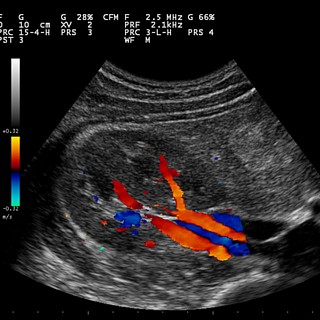

- Echographe portable médecine humaine.Echographie Humaine Intérêt d’un échographe portable en échographie humaine ? Médecine générale urologie ou autre , avoir cet appareil en hôpital pour vérifier les grossesses sans faire descendre la patiente a l’ échographie et faire la queue, limiter les risques de complication, trier les patients nous distribuons ce matériel en France et a l’ étranger avec des garanties pièce et main d’oeuvre de 2 années.

- Echographes Doppler couleurEchographe portable tous les échographes portables en veto et humaine [vc_accordion collapsible= »yes » disable_keyboard= »yes » active_tab= »0″][vc_accordion_tab title= »En savoir plus.. »][vc_column_text] Mob: +33633101107 Tel: +33148723771 Echographe portable tous nos échographes portables en medecine veto et humaine l’ échographe portable tous nos echographes portables pour toute médecine est un outil indispensable dans cette forte demande de diagnostic ambulatoire dans tous les domaines médicaux et toutes les spécialités , il peux se décliner dans la médecine humaine et vétérinaire. un échographe portable est si nécessaire dans les services de gynécologie obstétrique pour des inspections rapides et non traumatisante , j’ ai souvent été étonné de l’ intérêt du personnel hospitalier quand nous faisions des démonstration a l’ hôpital , ici nous voyons le premier échographe que j’ ai vendu en humaine , nous avions fait la démonstration sur une femme avec des douleurs épigastriques , elle était difficilement déplaçable a l’ échographie , c’ était donc un plus en terme de confort du diagnostic . @ contact: medical@echographes.fr [/vc_column_text][/vc_accordion_tab][/vc_accordion] Echographe portable 5/5 (100.00%) 5 votes

Le format notebook rend l' échographie mobile tres pratique en raison du fait qu'une batterie assure une totale indépendance, cet échographe a été vendu la première fois a la clinique des ursulines a Versailles a deux gynécologues et a été...